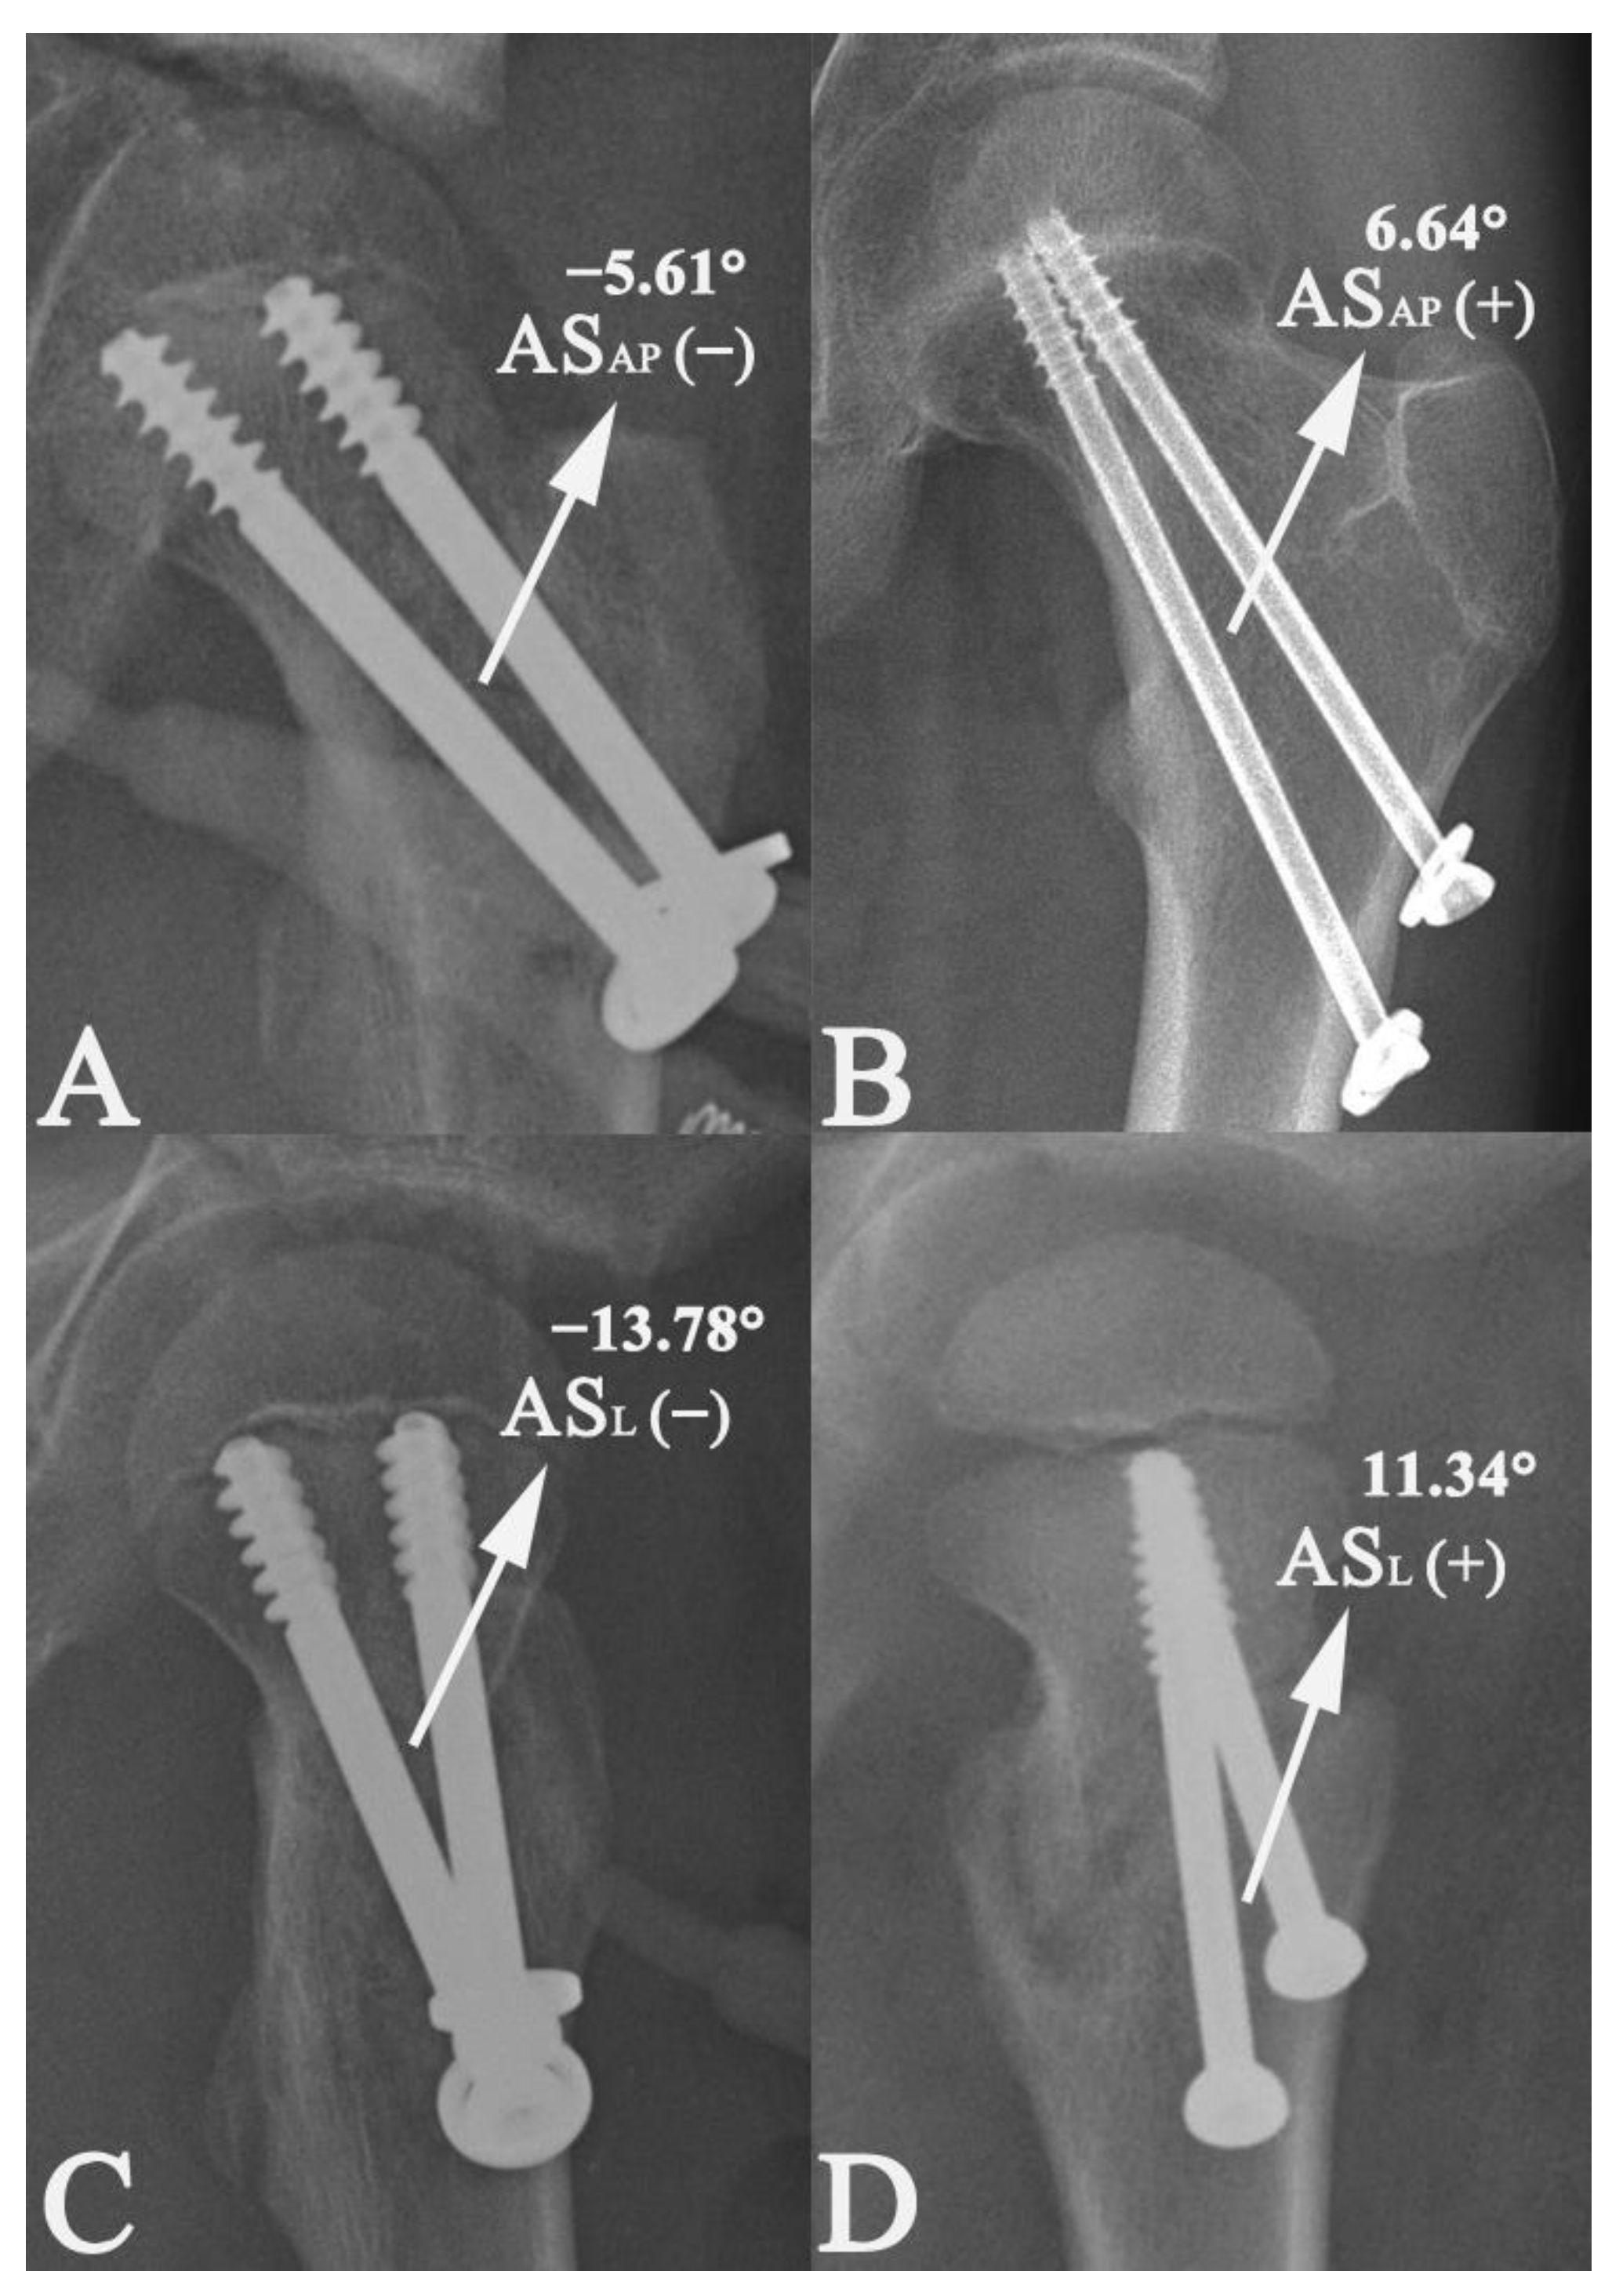

| ASAP (°) | −0.047 | 0.041 | −1.140 | 0.257 | −0.129, 0.035 |

| ASL (°) | −0.021 | 0.035 | −0.605 | 0.547 | −0.090, 0.048 |